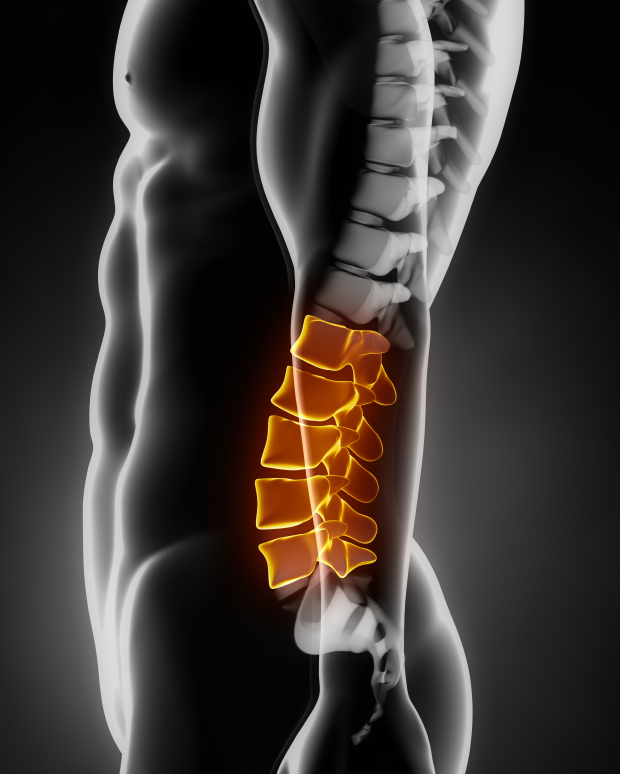

Lumbar Spine – TrialExhibits Inc.

Anatomy of the Lumbar Spine – TrialExhibits Inc.

Learn all about lumbar spine anatomy from a world-renowned Spine Expert …